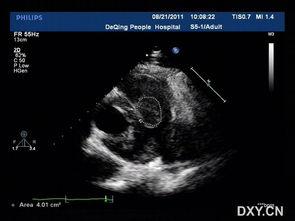

成人心脏超声,顾名思义,就是利用超声波技术对成年人心脏进行检查的一种无创、安全、便捷的检查方法。它能够清晰地显示心脏的结构、功能以及血流情况,对于心脏疾病的诊断和治疗具有重要意义。